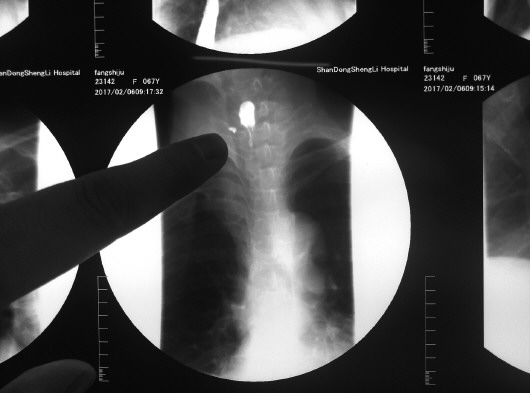

从房老太的片子上,能清楚地看到枣核的样子。 本报记者 孔雨童 摄

本报济南2月13日讯(记者 孔雨童) 过年吃个年糕本来是充满喜气的事,但济南长清68岁的房老太却经历了一场惊险。因为误把一颗大枣囫囵吞下,枣核刺破房老太食道造成穿孔,险些波及纵隔大血管。

2月13日,刚刚出院的房老太还不能正常饮食。她介绍说,自己正月初五去亲戚家吃饭,吃年糕的时候一颗大枣掉到了粥里,自己不小心就吞下去了。接下来的几天里,她常常感觉到脖子里一阵阵剧痛。“我还以为是枣子划破了食道,所以也没在意。”没想到脖子疼得越来越厉害,她去了当地医院检查,发现一颗大枣核卡在了食道里,而且把食道壁给穿破了。

由于手术风险太大,房老太被转到了省立医院西院,通过食道镜才把枣核取出。

“纵隔处有很多从心脏出来的大血管,枣核一旦刺破食道壁就有生命危险。”省立医院西院头颈外科医生田家军介绍,房老太还属于比较幸运的,此前有一名同样被枣核刺破食道的烟台患者,因为枣核大部分穿出食道用食道镜无法取出,而不得不经开胸手术取出。